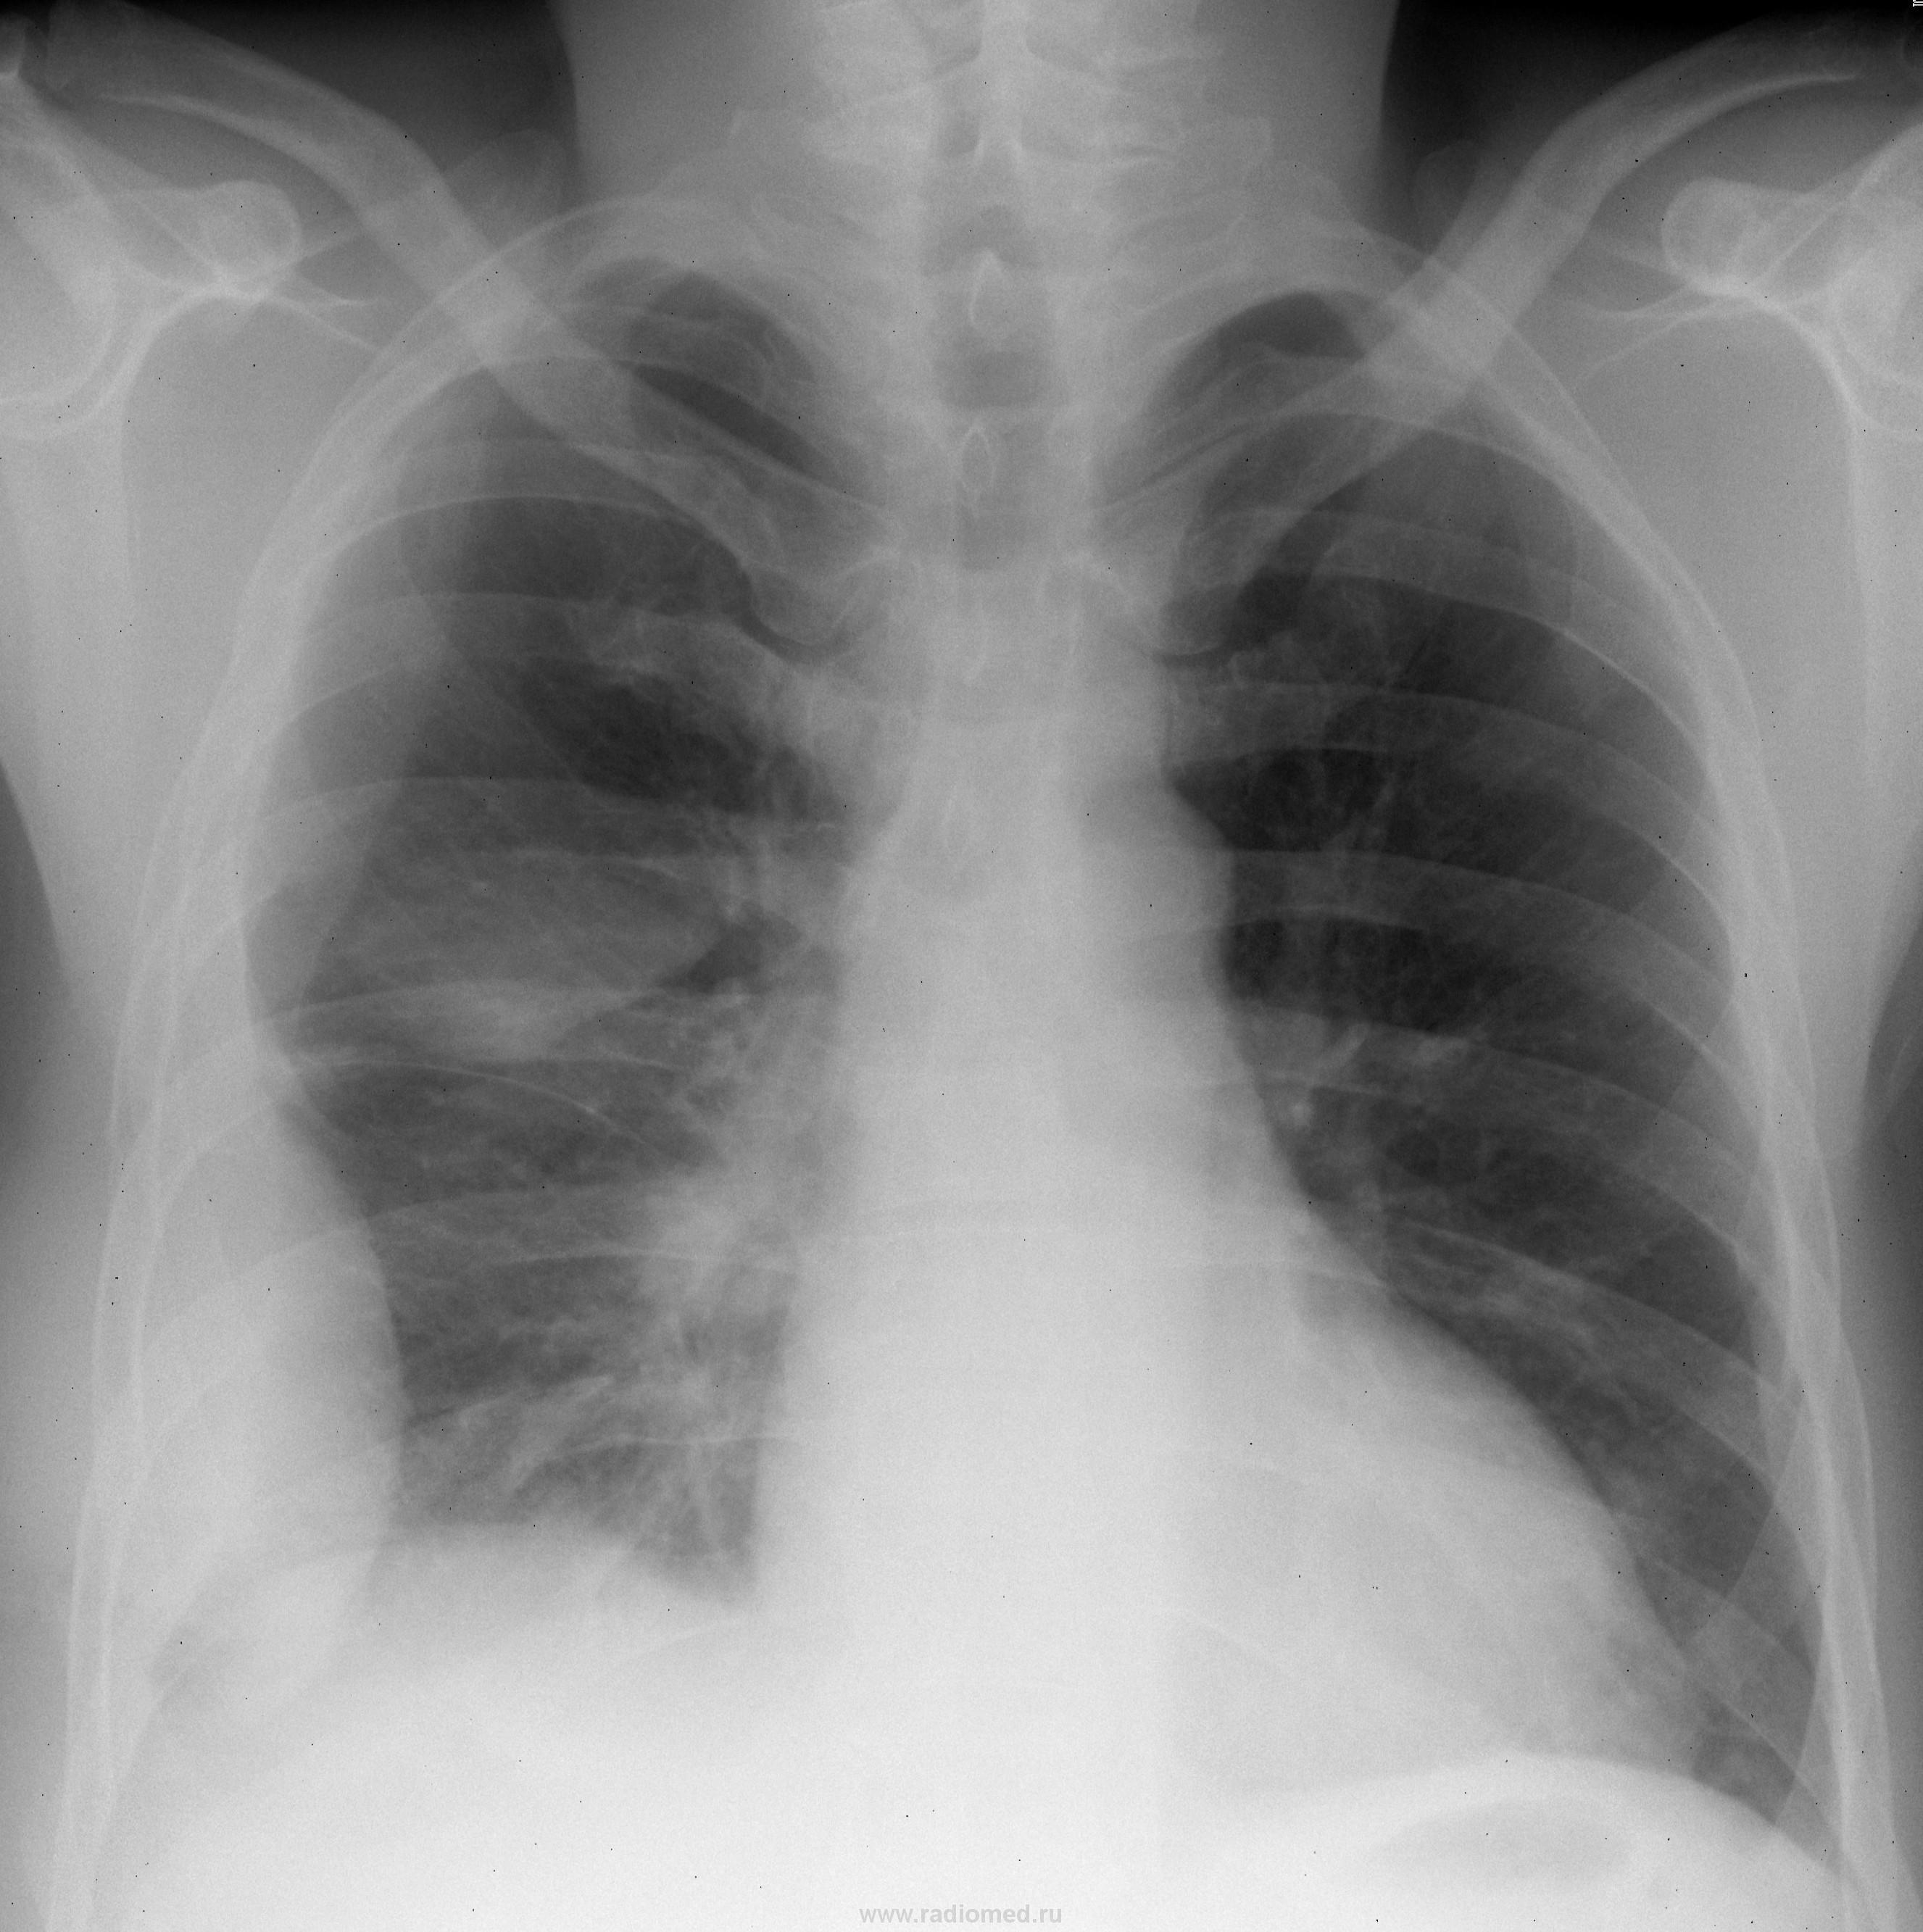

Пол пациента: Мужской пол Тип патологии: Другое Область исследования: Грудная клетка и верхние дыхательные пути Методы исследования: Rg Мужчина 50 лет. Жалобы на одышку, недомогание, боль в грудной клетке. Лабораторных показателей нет. https://radiomed.ru/sites/default/files/styles/case_slider_image/public/user/837/00000321.JPG?itok=c3sQzWdN ID:2384 Tue, 30/03/2010 - 20:13 #1 Катенёв Валенти... Offline Last seen: 7 years 3 months ago Joined: 22.03.2008 - 22:15 Posts: 54876 Паракостальный правосторонний осумкованные выпоты - латеральный и небольшой задний. Правосторонний интерлобарный в верхних отделах главной междолевой щели. По всей видимости и базальный (наддиафрагмальный) осумкованный. Tue, 30/03/2010 - 20:23 #2 brainmodel Offline Last seen: 4 months 4 weeks ago Joined: 18.03.2010 - 22:04 Posts: 2881 Осумкование плеврита: по боковой, задней поверхности, задней междолевой. Наддиафрагмальный компонент. Короче, повторяю слова В.Л. Verum plus uno esse non potest. Tue, 30/03/2010 - 21:05 #3 Грицько Виталий Offline Last seen: 9 years 2 months ago Joined: 05.01.2010 - 14:06 Posts: 1058 Согласен с коллегами. А на корень справа в динамике внимание бы обратил. Tue, 30/03/2010 - 21:21 #4 Катенёв Валенти... Offline Last seen: 7 years 3 months ago Joined: 22.03.2008 - 22:15 Posts: 54876 Грицько Виталий wrote: Согласен с коллегами. А на корень справа в динамике внимание бы обратил. В динамике - "да". Но лучше оттомографировать. Sat, 04/03/2017 - 23:51 #5 Катенёв Валенти... Offline Last seen: 7 years 3 months ago Joined: 22.03.2008 - 22:15 Posts: 54876 Интересное наблюдение.

Паракостальный правосторонний осумкованные выпоты - латеральный и небольшой задний. Правосторонний интерлобарный в верхних отделах главной междолевой щели. По всей видимости и базальный (наддиафрагмальный) осумкованный.

Осумкование плеврита: по боковой, задней поверхности, задней междолевой. Наддиафрагмальный компонент. Короче, повторяю слова В.Л.

Согласен с коллегами. А на корень справа в динамике внимание бы обратил.

В динамике - "да". Но лучше оттомографировать.